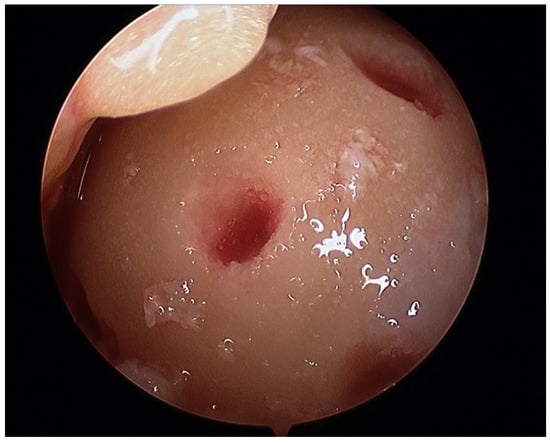

2.2. Surgical Procedure